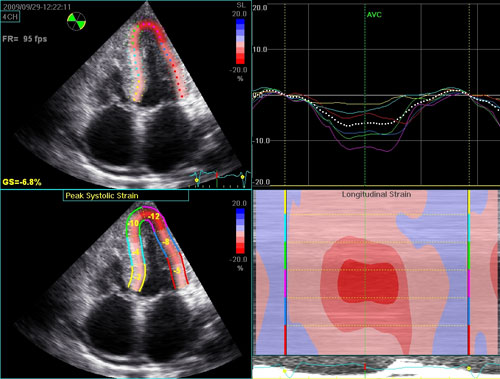

4-Chamber Strain

Typical echocardiogram for a patient with AL amyloidosis. There is biventricular wall thickening with normal cavity size, and bi-atrial enlargement. The atria are immobile, best noted on the apical 4-chamber view. Despite the normal left ventricular ejection fraction, longitudinal function is significantly impaired, as noted on the tissue Doppler and on the color map of longitudinal strain.